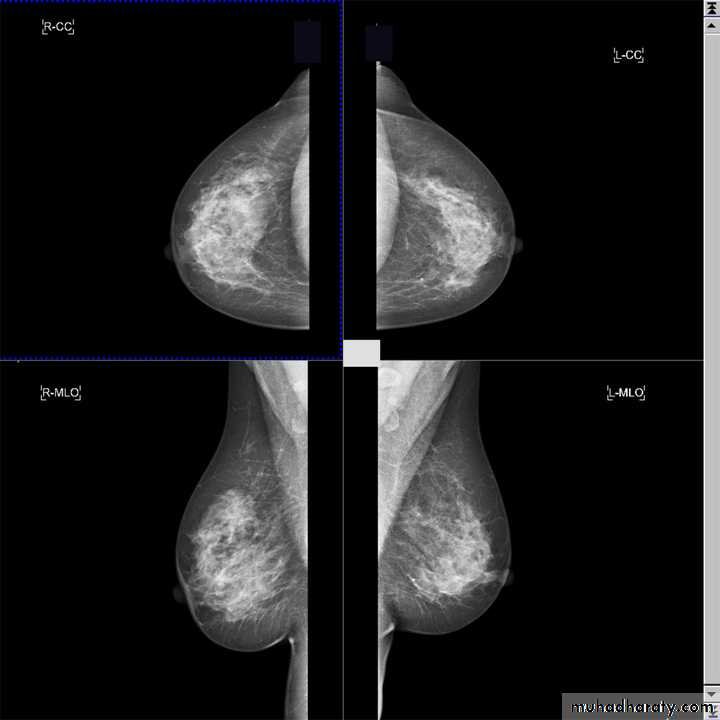

Alkindy college of medicine, university of BaghdadThe two standard views are :.

craniocaudal view (CC view)mediolateral oblique view (MLO view)

:Adequate craniocaudal views

all glandular tissue identifiednipple in profile

nipple in midline of image

images symmetric

Adequate medio-lateral oblique views

pectoral shadow seen down to level of nipple or lowerinframammary fold well seen

nipple in profile